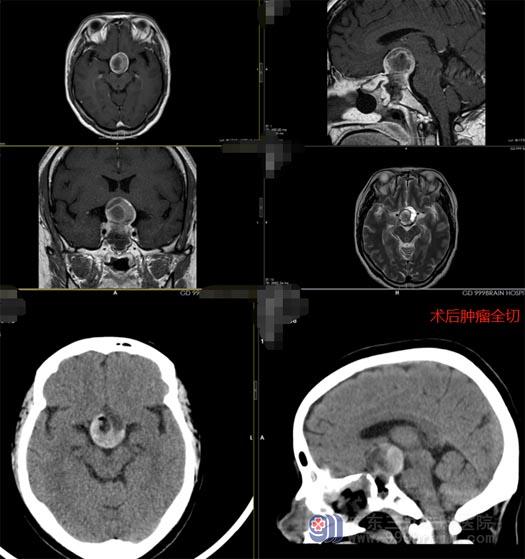

鲁明副院长、王国良主任带领神经外五科内镜组团队进行病例讨论,一致决定为病人行内镜经鼻蝶鞍区占位病变切除术,传统的手术方法,需采取开颅入路,手术创伤较大,耗时较长,并发症较多。相比之下经鼻蝶手术创伤小,时间短、术后恢复快。家属同意后,立即安排了手术,手术过程非常顺利。

第二天,谭女士的精神状态及肢体活动情况都很好,视野也恢复了,很快就可以出院。家属非常感谢医生,也庆幸自己当初没有放弃。

▲术后